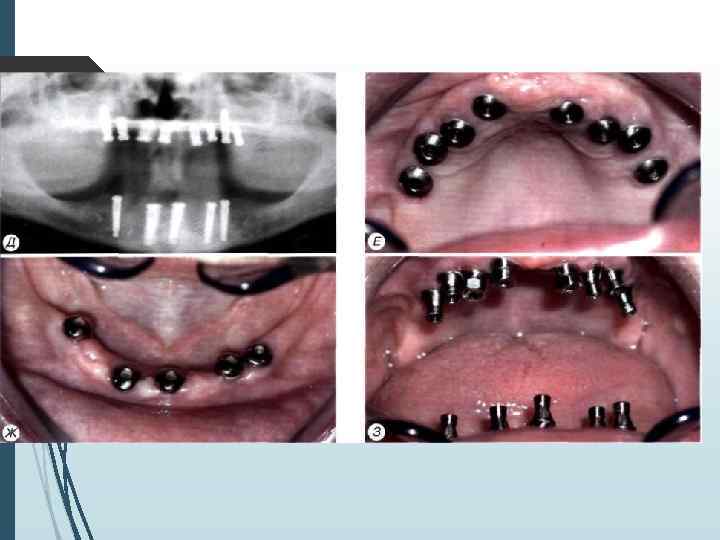

Двухэтапная методика имплантации I этап Произведя разрез и отслойку слизието-надкостничных лоскутов, приступают к формированию костного ложа иод имплантат с использованием общепринятых принципов атравматнчного препарирования кости. Сверлом диаметром неболее 2 2. 5 мм препарируют направляющий канал в кости на глубину, соответствующую высоте внутрикостного элемента (рис. 11 -2. 11 -3). Формирование направляющего канала необходимо для создания ориентиров расположения и направления вертикальной оси устанавливаемого имплантата. Затем этот канал расширяют при помощи сверла, диаметр которого не превышает 3 -3, 5 мм. Если диаметр внутри костной части имплантата составляет более 3. 5 мм, производят дополнительное препарирование сверлом соответствующего диаметра.

А препарирование направляющего канала фрезой Линденмана диаметром 2, 3 мм; 6 — расширение направляющего канала фрезой диамефом 3, 5 мм: В — расширение ложа фрезой диаметром 4. 0 мм:

Г — окончательное формирование ложа метчиком: Д установка внутрикостного элемента; Е установка винта-заглушки внутрикостно!о элемента:

Ж — закрытие операционной раны

// этап Второй этап операции проводят через 2 3 мес. после установки внутрикостных элементов. Под местной инфи. тьтрапионной анестезией при помощи зонда определяют расположение внутрикостных элементов под слизистой оболочкой. Если из-за значительной ее толщины или нарастания костной ткани на внутрикост-ную часть и заглушку Определить расположение имплантата зондом невозможно, необходимо произвести разрез слизистой оболочки длиной до 10 мм в месте, где должен находиться внутрикостный элемент. Затем, отслаивая слизистую оболочку определяют расположение имплантата визуально. Иссечение слизистой оболочки над внутрикостным элементом производят перфоратором и удаляют иссеченный участок (рис. 11 -5). Выкручивают заглушку. Промывают внутренний резьбовой канал имплантата. Ввинчивают формирователь десневой манжетки, который на ортопедическом этапе. течения заменяют на опорную головку. Если производился разрез, рану зашивают узловыми швами.

А —- иссечение перфоратором слизистой оболочки и надкостницы над внутрикостным элементом; Б — выкручивание винта-заглушки: В — установка формирователя десневой манжетки